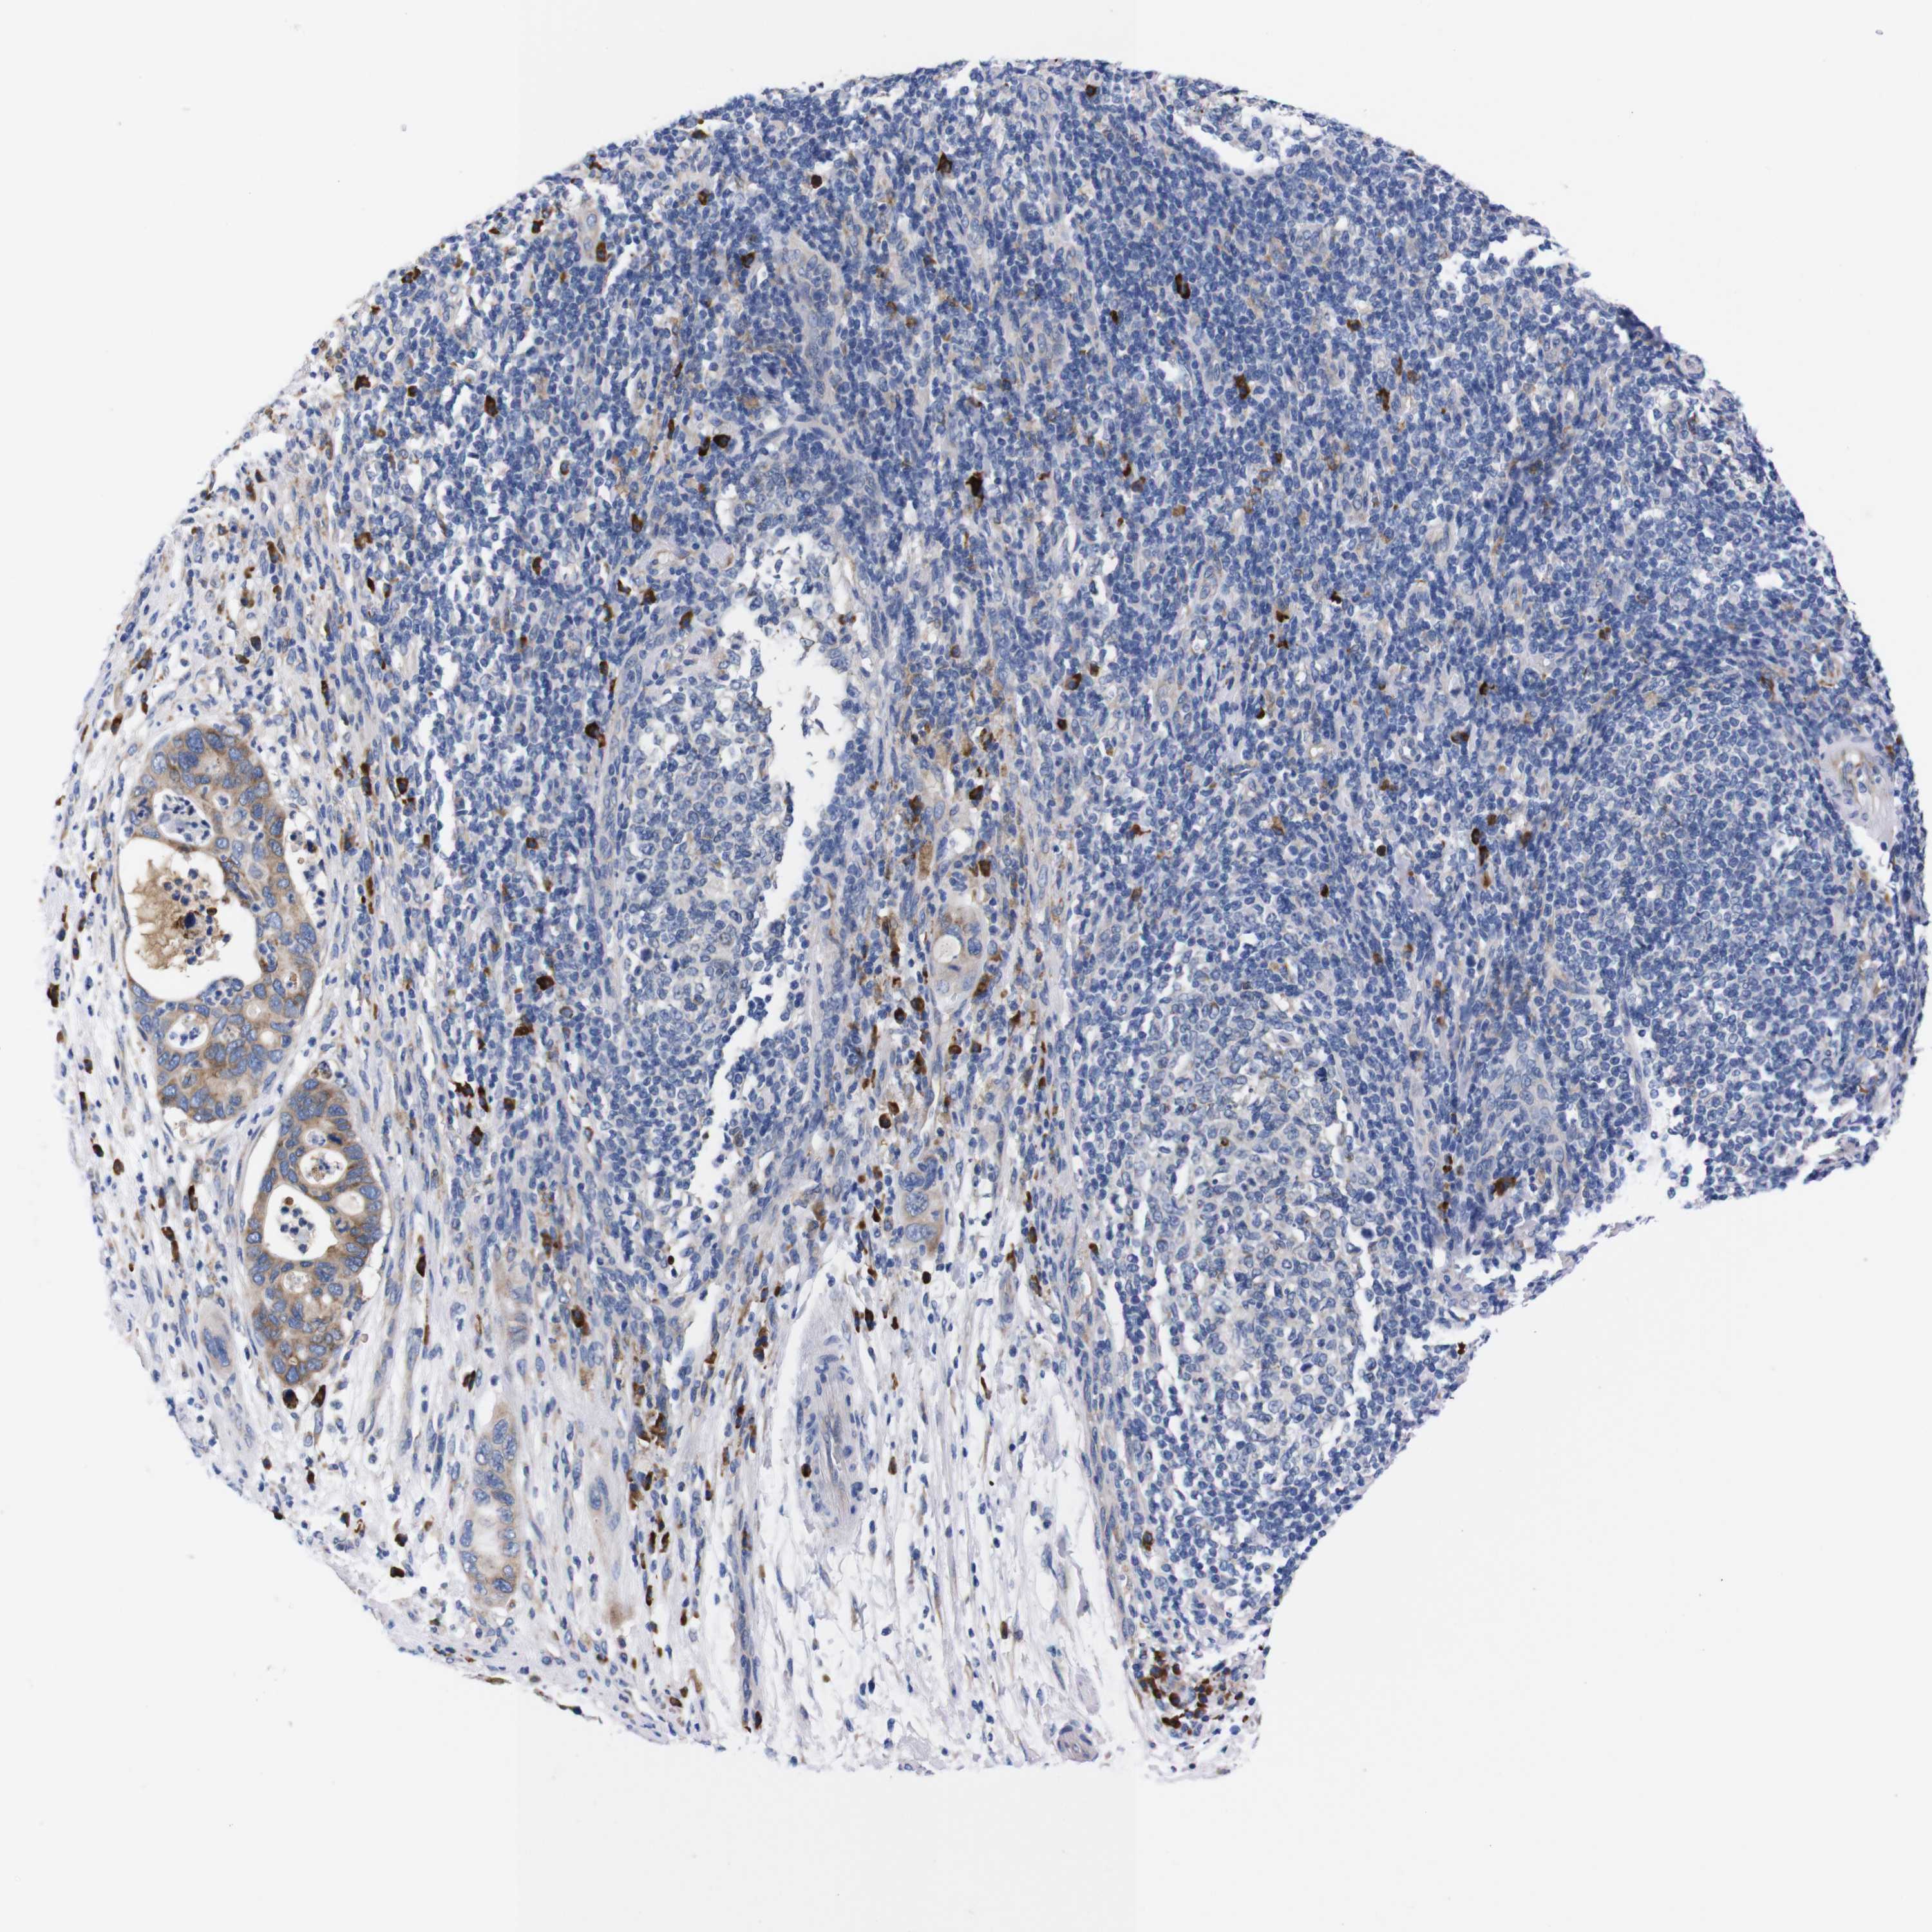

PANCREATIC CANCER - Protein expressioni

A mouse-over function shows sample information and annotation data. Click on an image to view it in a full screen mode. Samples can be filtered based on level of antibody staining by selecting one or several of the following categories: high, medium, low and not detected. The assay and annotation is described here.

Note that samples used for immunohistochemistry by the Human Protein Atlas do not correspond to samples in the TCGA dataset.

Antibody stainingi

Antibody staining in the annotated cell types in the current human tissue is reported as not detected, low, medium, or high, based on conventional immunohistochemistry profiling in selected tissues. This score is based on the combination of the staining intensity and fraction of stained cells.

Each image is clickable and will lead to virtual microscopy that enables deeper exploration of all samples and also displays staining intensity scores, fraction scores and subcellular localization as well as patient and tissue information for each sample.

Antibody HPA013994

Antibody HPA013995

Staining

High

Medium

Low

Not detected

Intensity

Strong

Moderate

Weak

Negative

Quantity

>75%

75%-25%

<25%

None

Location

Nuclear

Cytoplasmic/membranous

Cytoplasmic/membranous,nuclear

Adenocarcinoma, NOS